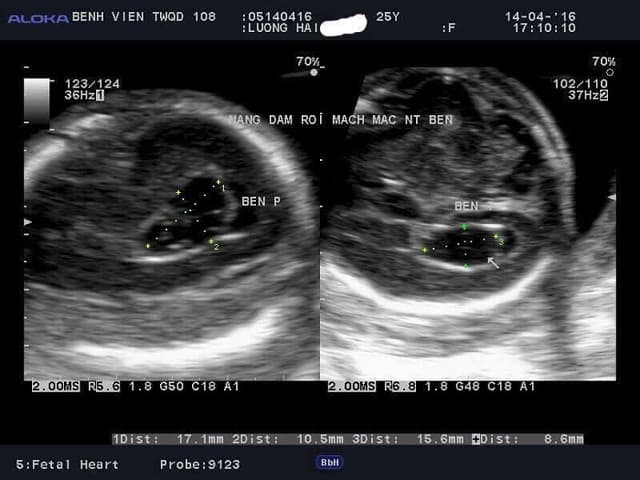

Nốt vôi hóa trong tim thai có nguy hiểm?

Chào bác sĩ! Bác sĩ cho cháu hỏi: Nốt vôi hóa trong tim thai có nguy hiểm không ạ? Cháu đi siêu âm lúc thai 21 tuần. Bác sĩ bảo tất cả bình thường nhưng ở thất trái tim thai có nốt vôi hóa nhưng vẫn trong giới hạn cho phép, bảo cháu không cần […]